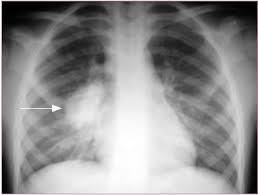

Rx: derrame pleural, pneumonia redonda “pseudotumoral”, abscesso

Radiografia de tórax:

Rx: broncopneumonia ou lobar

Organismos causadores de pneumonia capazes de evoluir com abscesso (> 2 cm)?

Anaeróbios: doença periodontal, broncoaspiração, alcoolismo, distúrbios deglutição

S. aureus: drogas IV, endocardite, fibrose cistica, neonatos

Klebsiella: etilistas, DM